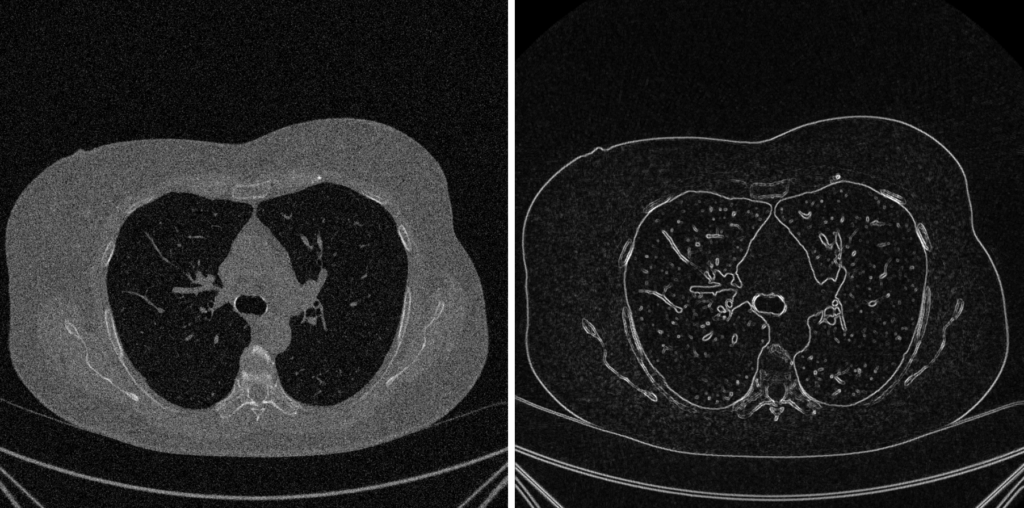

2. Sharpening: Evidenziare Bordi e Dettagli

Lo sharpening è l’opposto del denoising: mira a enfatizzare le alte frequenze (transizioni nette).

Filtro di Sobel (Basato sulla Derivata Prima): Il filtro di Sobel è un operatore discreto di differenziazione che approssima il gradiente dell’intensità dell’immagine. È primariamente impiegato per l’edge detection (rilevamento dei bordi), identificando i punti di massimo cambiamento di intensità.

Pro: Semplicità concettuale e rapidità di calcolo; fornisce sia l’intensità che l’orientamento del gradiente; incorpora un leggero effetto di smoothing che attenua il rumore.

Contro: Rimane suscettibile al rumore ad alta frequenza.I bordi rilevati sono spesso spessi (multi-pixel). Non è l’operatore più accurato per la localizzazione esatta del bordo (spesso si preferisce l’algoritmo di Canny).

Filtro di Laplace (Basato sulla Derivata Seconda): è un operatore di derivata seconda utilizzato per l’individuazione dei bordi nelle immagini. Funziona misurando la “curvatura” o la rapidità di cambiamento dell’intensità di un pixel rispetto ai suoi vicini, rilevando così linee sottili e bruschi cambiamenti. Lo sharpening dell’immagine è ottenuto sottraendo il Laplaciano dall’immagine originale.

Pro: Sensibilità ai dettagli; semplice e veloce

Contro: Sensibilità al rumore ad alta frequenza; A differenza del gradiente (derivate prime), non fornisce informazioni sulla direzione del bordo.

I Giudici della Qualità: PSNR e SSIM

Valutazione della Qualità: L’Occhio del Matematico vs. L’Occhio del Radiologo

Abbiamo completato la nostra catena di elaborazione. Ora, come facciamo a sapere se il nostro risultato è “migliore”? Ci affidiamo a metriche quantitative che confrontano la nostra immagine elaborata con un’immagine di riferimento ideale (la ground truth).

1. PSNR (Peak Signal-to-Noise Ratio): il Matematico

Il PSNR è la metrica “classica” e puramente quantitativa.

- Cosa Misura: La fedeltà numerica. Si basa sull’Errore Quadratico Medio (MSE), che calcola la differenza, pixel per pixel.

- Obiettivo: Massimizzare il PSNR. Un PSNR più alto significa un MSE più basso (errore numerico minore).

2. SSIM (Structural Similarity Index): il Radiologo

L’SSIM è una metrica moderna e percettiva, progettata per imitare il modo in cui un essere umano (come un radiologo) giudica la qualità di un’immagine.

- Cosa Misura: La somiglianza strutturale. L’SSIM riconosce che l’occhio umano è molto più bravo a percepire strutture e relazioni tra i pixel che a notare piccoli errori numerici.

- Come funziona: Invece di confrontare singoli pixel, confronta piccole finestre (patch) di immagine, valutando tre componenti chiave:

- Luminanza: Il livello medio di intensità è simile?

- Contrasto: La varianza locale dei dettagli è simile?

- Struttura: Il pattern dei pixel (quindi la loro correlazione) è simile?

- Obiettivo: Massimizzare l’SSIM (il cui valore va da -1 a 1, dove 1 è identità perfetta).

Conclusione: Il Trade-Off Diagnostico

Qui sta il punto cruciale dell’intero imaging scientifico:

Un PSNR alto non significa sempre un’immagine diagnosticamente migliore.

Immaginiamo un filtro di denoising molto aggressivo (es. un forte blur Gaussiano). Questo filtro “spalma” il rumore, riducendo drasticamente l’errore numerico (l’MSE) e portando a un PSNR altissimo.

Tuttavia, nel processo, quel filtro ha anche “spalmato” una micro-lesione o una linea di frattura sottile. Ha distrutto la struttura.

- PSNR: Alto (il matematico è felice, l’errore medio è basso).

- SSIM: Basso (il radiologo è scontento, il dettaglio strutturale è perso).

- Valore Diagnostico: Nullo.

Il vero obiettivo dello sviluppo di algoritmi (come NLM o Wavelet Denoising) non è massimizzare ciecamente il PSNR, ma trovare il perfetto trade-off: un algoritmo che riduca il rumore (aumentando il PSNR) preservando al contempo i dettagli critici (mantenendo alto l’SSIM).